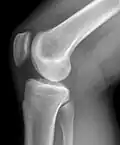

Рентгенограмма коленного сустава в боковой проекции.

Рентгенологическое исследование коленных суставов

Самым доступным, одним из информативных и распространённых исследований является рентгенологическое исследование.

Стандартные проекции, применяемые при рентгенографии коленного сустава — прямая (передне-задняя) и боковая. По мере необходимости их дополняют правой или левой косой, а также аксиальной проекциями. Основным правилом при рентгенологическом исследовании коленного сустава является полипозиционность[2][3].